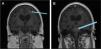

In October 2018, the patient underwent an allogeneic HSCT from a 10/10 HLA-matched unrelated donor. A pre-transplant MRI was performed one month before transplant that found no enhancements to suggest any active disease (Figure 2). She underwent pre-transplant conditioning with fludarabine, treosulfan, and cytarabine (Cytarabine). Neutrophil and platelet engraftment took place 15 days post-transplant. Tacrolimus, rabbit anti-thymocyte globulin, methylprednisolone, and methotrexate (Methotrexate) were given for graft-versus-host disease (GvHD) prophylaxis. She developed acute GvHD (overall Grade I) of the skin and gut, which resolved with topical and systemic steroids. Chimerism 60 days post-transplant showed >95 % donor cells, and at 280 days post-transplant the patient demonstrated stable chimerism with CD3 donor cells at 97.4 %, CD19 at 98.9 %, and myeloid cells at 98 %, and remained at these levels thereafter.

DiscussionIsolated CNS symptoms in the absence of systemic manifestations makes differentiating CNS-HLH from other CNS inflammatory diseases, such as ADEM, extremely challenging, as seen in this case. A study conducted by Deiva et al. compared radiological presentations of CNS-isolated HLH and ADEM and found that while both may present with white matter hyperintensity on MRI, CNS-HLH often features symmetrical, periventricular lesions, whereas ADEM typically involves the brainstem [8]. Our patient had asymmetrical white matter lesions and brainstem involvement, demonstrating that additional studies are necessary to fully differentiate these conditions (Figure 2).